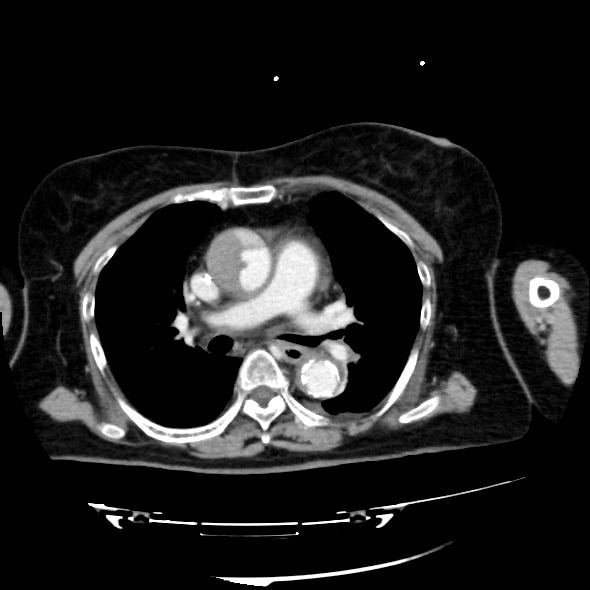

急性大動脈解離の造影CT

70歳代、女性、54kg、Stanford A型急性大動脈解離

症例は70歳台女性。胸背部痛を主訴に近医を受診し、単純CTを撮像したところ、Stanford A型急性大動脈解離を認めたため、加療目的に当院へ転院搬送となった。既往に慢性腎臓病があり、Cre 2.43mg/dL、eGFR 15.7と高度腎機能障害を認めたが、リスクベネフィットを検討した結果、術前精査のために造影CTが施行された。解離の範囲や造影剤のエントリー部位を同定することができた。

造影CTは急性大動脈解離の診断において最重要の検査であり、真腔と偽腔の描出、エントリー部位や偽腔内血栓の有無を評価できる。また、MPRや3D再構成を用いることで大動脈全体や末梢血管の状態を把握でき、手術やInterventional Radiologyによる手技前の血管解剖評価にも有用である。さらに、造影効果不良域の検出、ULP(ulcer-like projection)、臓器梗塞も早期に発見可能である。このように、造影CTは非侵襲的で短時間で行えるため、緊急疾患である急性大動脈解離に最適なモダリティといえる。一方で注意点は、造影剤アレルギーや腎障害など副作用への配慮、適切なプロトコル設計が求められる点である。造影CTは急性大動脈解離の確定診断と治療方針決定に不可欠であり、有効性を活かしつつリスク管理を徹底して施行する必要がある。